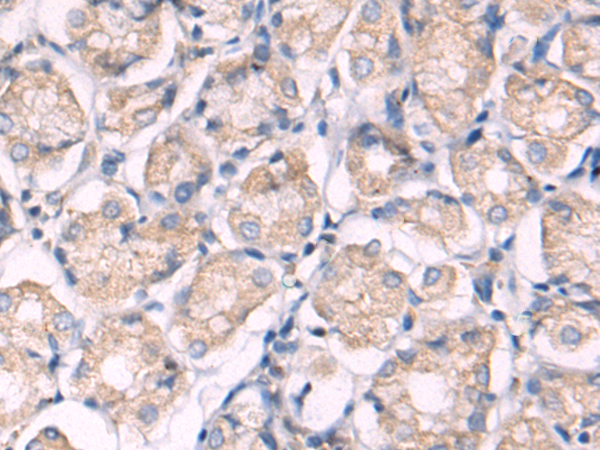

分类: 科研抗体货号: P08110别名:应用: IHC反应种属: Human

分类: 科研抗体货号: P08130别名: BTLA1; CD272应用: WB,IHC反应种属: Human